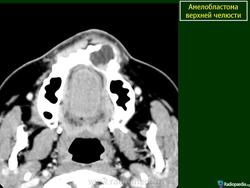

Амелобластома - доброкачественная одонтогенная эпителиальная опухоль, способная к инвазивному росту. Развивается внутри кости, по микроструктуре напоминает стадии развития эмалевого органа, наблюдается чаще у лиц среднего возраста, в 80% случаев поражает тело нижней челюсти в области моляров и премоляров, а также угол и ветвь нижней челюсти. Редко она обнаруживается в области резцов. Проявляется чаще в возрасте 20-50 лет с одинаковой частотой у лиц обоего полу, может встречаться и у детей.

Амелобластома

ID: 3992 Ameloblastoma - maxillary Dr Frank Gaillard - 7 Jul 2008 CT through the maxilla obtained with contrast demonstrates a cystic lesi...